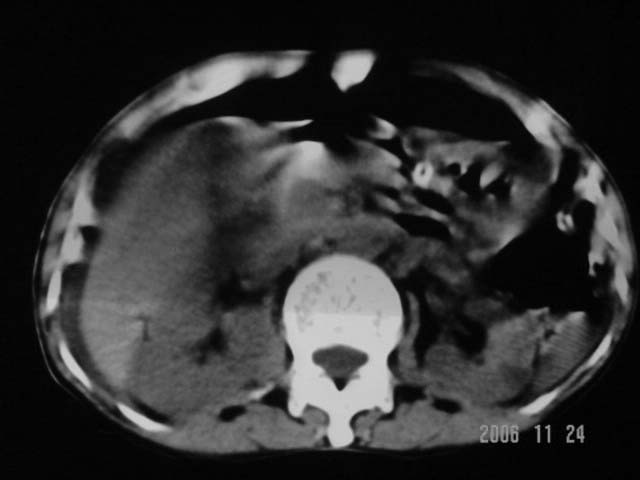

仰卧位见:肝前间隙及肝脾间隙内可见新月形气体密度影,边缘清楚,侧卧位见气体随体位改变而移动,ct值约-929hu。膈下、肝下间隙及部分肠间隙可见液性密度影。考虑:1、上腹部空腔脏器穿孔,以胃穿孔可能性大。2、少量腹水。

仰卧位见:肝前间隙及肝脾间隙内可见新月形气体密度影,边缘清楚,侧卧位见气体随体位改变而移动,ct值约-929hu。膈下、肝下间隙及部分肠间隙可见液性密度影。考虑:1、上腹部空腔脏器穿孔,结合临床,首先考虑胃穿孔可能性大。2、少量腹水

补充--肝门及肝肾间隙以见积气显示。

支持消化道空腔脏器穿孔(腹腔内大量游离气体影,小网膜囊内亦见气体影),少量腹水。